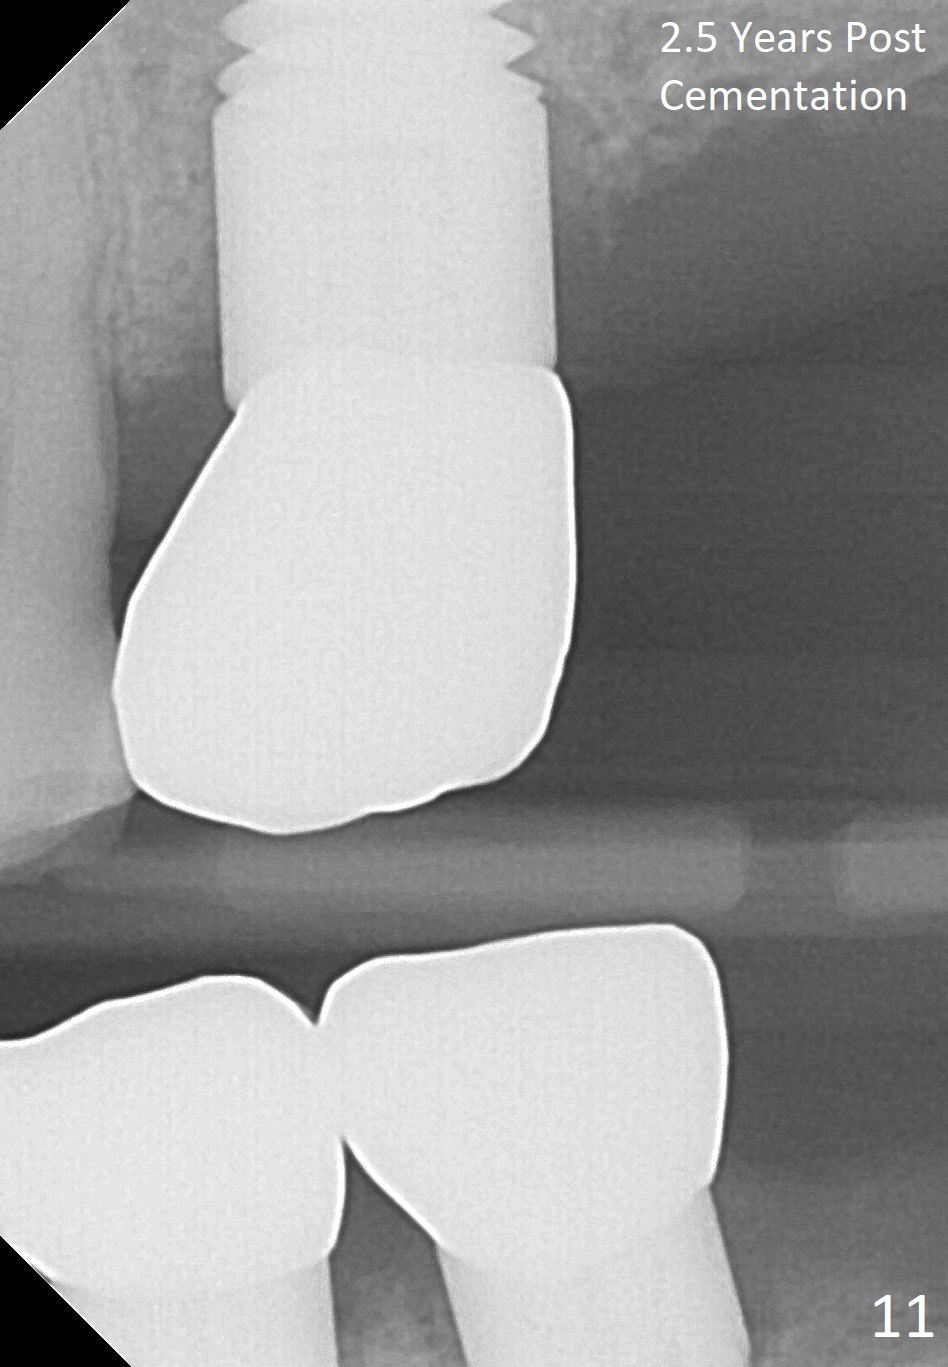

Fig.5 is an illustration showing the socket after extraction. The osteotomy is intentionally placed distally (Fig.6 arrow: pilot drill). In case the patient agrees to have ortho treatment, there will be space to correct the upper midline (7). If not, a molar crown will be fabricated. By the time a 4.5x20 mm tap is inserted (Fig.7 T), the mesial gap is visible (*). When a 6x20 mm implant is placed (Fig.8 I), bone graft is placed buccally (Fig.2, as planned) and mesially (Fig.8 red circles, as compared to Fig.1). The implant has to be as large and long as 6x20 mm to get primary stability (insertion torque 50/60 Ncm). The apex of the implant is close to the sinus floor (Fig.8 ^) or in fact the nasal floor (Fig.9 N). There appears bone growth in the mesial gap 3 months postop (Fig.10 *). There is no bone loss 2.5 years post cementation (Fig.11).